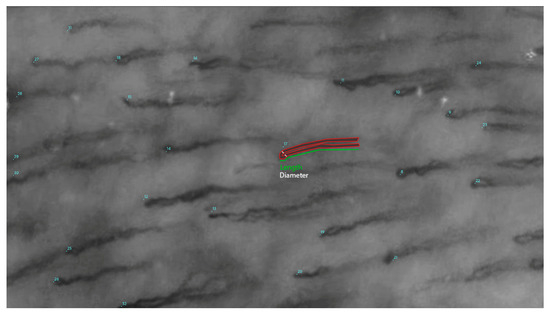

In addition to its methodological contributions, this study has important implications for the field of microvascular research. The oral mucosa, with its accessibility and rich microvascular network, serves as an ideal model for studying systemic microvascular changes. By improving our ability to measure and analyze capillary morphology (Figure 2), this research has the potential to enhance our understanding of a wide range of diseases, from periodontal disorders to systemic conditions such as diabetes, autoimmune conditions, and cardiovascular disease. Furthermore, the development of reliable automated methods could pave the way for more widespread use of microvascular assessment in clinical settings, enabling earlier detection and more effective management of microvascular pathologies.

Figure 2.

Frame of a videocapillaroscopy with highlighted parameters.